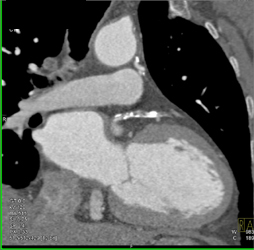

Internal Mammary Artery-look Good